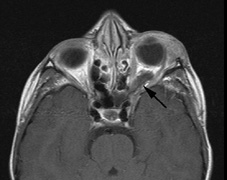

The PWS may not entirely respect the midline, possibly a reflection of transmedian innervation.212 The lesion grows proportionally with the child, often becoming darker in color. 213 The overlying skin may develop nodularity or hypertrophy in two-thirds of patients (by the fifth decade).214 Treatment with a pulsed-dye laser may significantly improve the appearance, but recurrence (i.e., redarkening) is possible.215,216 A deficit in the number of perivascular nerves in port-wine stains suggests that abnormal neural modulation of vascular flow may be involved in their pathogenesis.217 Intracranial leptomeningeal capillary vascular malformation (Figs. 21 and 22) is associated with seizures and contralateral neuromuscular weakness. Central nervous system involvement correlates highly with ipsilateral involvement of the V1 dermatome by a PWS.208,218

It has been hypothesized that the calcific changes reflect cellular anoxic injury secondary to venous stasis/poor drainage.219,220 Abnormal autonomic innervation has also been reported in association with the malformed cortical vessels—innervation only by noradrenergic fibers.221 Studies suggest that the normal increase in brain-blood flow to accommodate increased metabolic demand during seizure activity is blunted in affected brain regions of SWS.222 Thus, seizures in the setting of impaired perfusion may be exacerbating brain injury. Periods of contralateral weakness (days to weeks) can follow a prolonged seizure episode.206,223 When seizures begin early in life, the risk of developmental delay is much higher. In a review of 171 patients with a facial PWS and associated intracranial vascular malformation, 80% were found to have a seizure disorder. Of those, 75% with seizures had an onset during the first year of life, rising to 95% before age 5 years. Nearly all patients had a PWS that included (or was limited to) the V1 distribution. Developmental delay was strongly associated with seizures (71% of children with seizures as compared to 6% without seizures).224 Glaucoma affects 50% to 70% of SWS patients224,225 and it is a therapeutic challenge. From the time of diagnosis, the intraocular pressure, the optic discs, and the corneal diameters need to be measured intermittently, even if an occasional examination under anesthetic is required. The development of glaucoma appears to follow a bimodal age distribution: early-onset/congenital-type and later-onset. The glaucomatous eye is nearly always on the same side as the PWS.224 The highest risk for glaucoma appears to be when the PWS involves both the upper and lower lid: 72% vs. 21% for VI-only (upper eyelid) involvement in one study.224 The bimodal age distribution of glaucoma suggests that more than one mechanism is involved. Angle abnormalities (“trabeculodysgenesis” with or without flat anterior iris insertion) have been reported in association with the early-onset/congential type.225 Other proposed mechanisms include uveal capillary dilation226 and elevated episcleral venous pressure. Reports of blood in Schlemm's canal on gonioscopy support the idea of increased episcleral venous pressure pathomechanics.227,228 Glaucoma in SWS often responds poorly to medical therapy alone. The “trabeculodysgenesis” of early onset Sturge-Webber glaucoma is reported to be similar in gonioscopic appearance to primary congenital glaucoma.229 On this basis, goniotomy was suggested as a treatment of choice in early-onset SWS glaucoma. One group looked at the success of goniotomy, trabeculotomy, trabeculectomy, laser trabeculoplasty and medication in the management of SWS-associated glaucoma.230 In the early onset subgroup receiving goniotomy, median stable interval of intraocular pressure reduction after one procedure was 8 months; with multiple goniotomies and the addition of medical treatment, the median stable interval was extended to 9 years. Other investigators have found that goniotomy alone may be insufficient, requiring filtering surgery at some point. However, trabeculectomy carries a significant risk of choroidal expansion in association with hypotony. Theoretically, the risk may be higher when there is increased choroidal vascularity in association with the facial PWS—a “tomato ketchup” fundus.231 Often, there is associated increased tortuosity of the retinal vessels as well. Placement of a prophylactic posterior sclerotomy prior to filtering surgery to prevent choroidal expansion is controversial.232 Cryo- or thermocoagulation of the ciliary body in combination with medical therapy may be an alternative to surgery.233 KLIPPEL TRENAUNAY—WEBER SYNDROME Klippel-Trenaunay syndrome consists of combined capillary, lymphatic, and venous malformations, in association with varicosities and limb enlargement (Fig. 23). In the majority of cases, the lower limb is affected.234,235